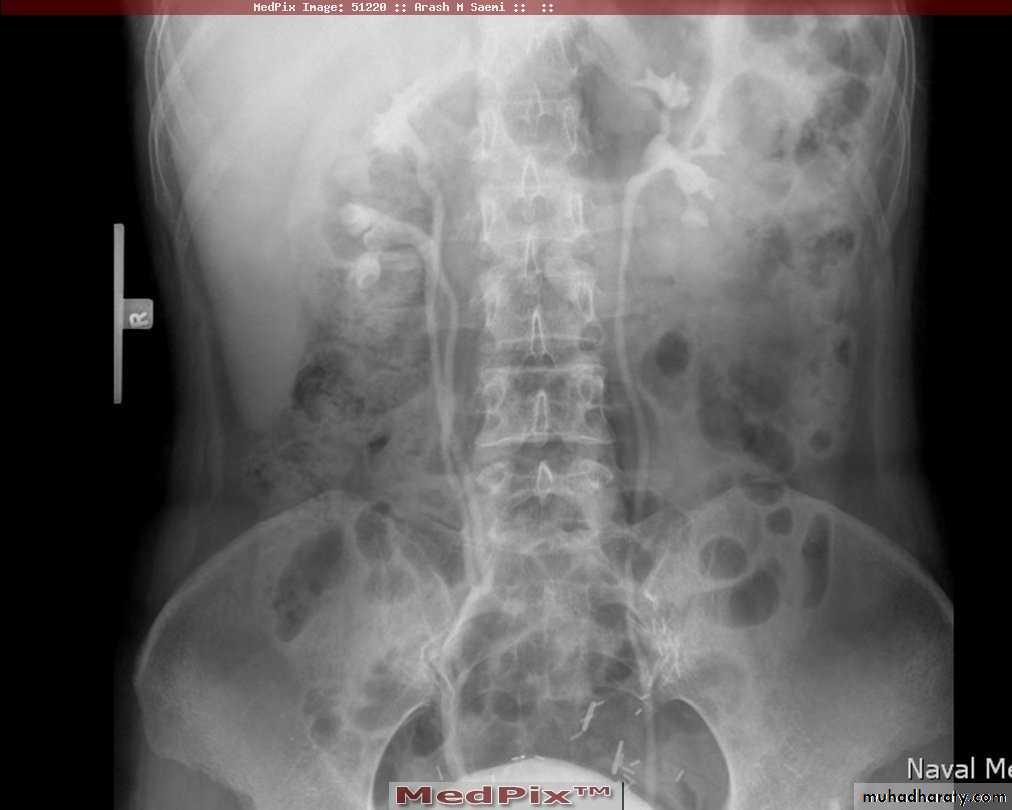

13- Polycystic